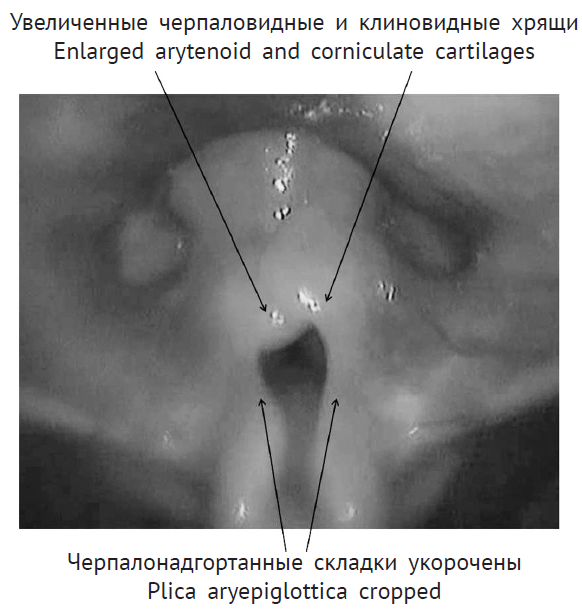

Для определения патологии гортани выполнена гибкая назофаринголарингоскопия (рис. 1).

Рис. 1. Эндофотография гортани. Врожденный порок развития гортани. Ларингомаляция 2-го типа

При назофаринголарингоскопии выявлены признаки ларингомаляции 2-го типа: надгортанник свернут в виде желоба, черпалонадгортанные складки укорочены, увеличенные черпаловидные и клиновидные хрящи выдвинуты вперед и прикрывают голосовой отдел гортани, подголосовой отдел не обозрим. Однако просвет гортани для дыхания в динамике сохранен, частичный коллапс преддверия гортани на вдохе за счет сближения краев надгортанника и пролабирования клиновидных хрящей. На рентгенограмме шеи в боковой проекции просвет подголосового отдела гортани и трахеи прослеживается на всем протяжении, не изменен (рис. 2). Кислотно-основное состояние крови — насыщение капиллярной крови кислородом 95,6 %